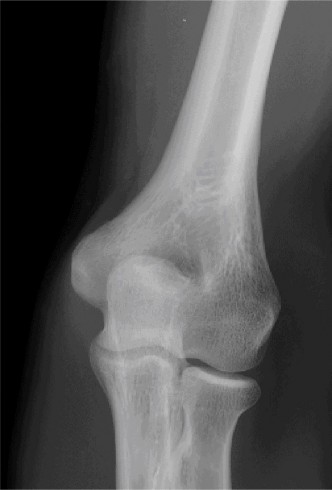

A 32-year-old male presented to the emergency department 1 hour after sustaining a fall while skateboarding. The patient complained of pain in the elbow with swelling and deformity present. He denied numbness or tingling.

Examination reveals deformity about the elbow with no open lesions or skin tenting. He has a palpable radial and ulnar pulse and is neurologically intact. His images are shown (Figs. 2–85 to 2–88).

Figure 2–87

The correct answer is (B). This is the most common type of elbow dislocation, and often does not cause any osseous injury. Posterolateral and posteromedial dislocation account for approximately 90% of dislocations. Adequate pre- and postreduction films are necessary to evaluate for fracture, which would change the classification to a complex injury.

The correct answer is (C). All patients with an elbow dislocation should be reduced on an urgent basis. It is important to document the neurovascular examination both pre- and post-reduction. Once reduced, the elbow should be taken through a range of motion to evaluate if and when the elbow subluxes or redislocates. This will allow for improved ability to rehab the patient safely. Adequate postreduction films are necessary to evaluate the concentricity of the joint, as well as to further look for fractures not seen on the injury films.